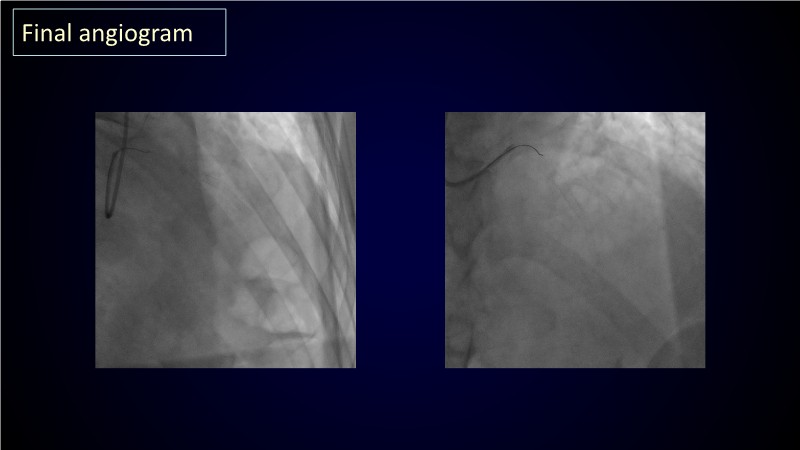

From planning the procedure and understanding calcium distribution, to lesion preparation with modern modification tools, and post-PCI assessment to confirm stent expansion and detect complications, this session demonstrates practical, imaging-driven strategies.

Learn how careful preparation and modern techniques improve outcomes in treating severe calcium, calcified nodules, and in-stent restenosis.